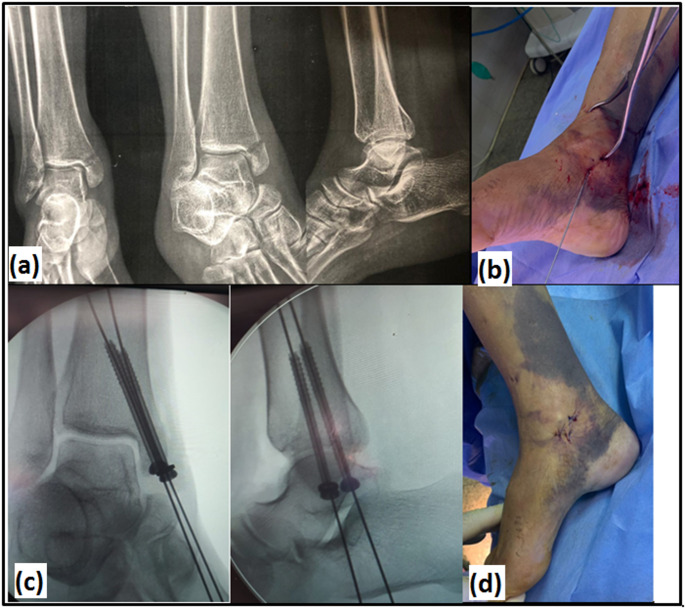

Introduction: Isolated medial malleolar (MM) fractures are infrequent injuries. Studies focused on their treatment are scarce. The aim of this study was to compare functional and radiographic outcomes of two surgical techniques for treatment of displaced isolated MM fractures in adults: closed reduction and percutaneous fixation (CRPF), and open reduction and internal fixation (ORIF) by using same implant; two partially-threaded cannulated cancellous screws.

Materials and methods: A prospective randomized controlled clinical trial (RCT) was conducted on 50 patients with isolated displaced MM fractures, treated with CRPF (group A) or ORIF (group B), at orthopaedics department of university hospital, from April 2021 to April 2023. Fractures were classified by Herscovici classification. The primary outcomes were incidence of complications and time to union based on radiographic assessment by plain radiographs of ankle. The secondary outcomes were functional assessment by Foot and Ankle Ability Measure (FAAM) for activities of daily living (ADLs) and sports, American Orthopaedic Foot and Ankle Society (AOFAS) score, and VAS.